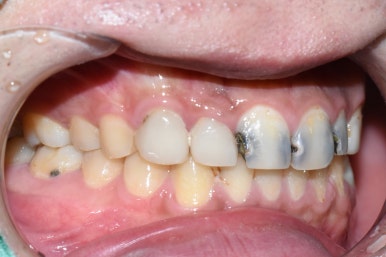

오늘은 치아가 "너무 많이 썩어서 부러졌어요, 앞니가 너무 많이 썩었는데 살릴 수 있을까요?"라는 용건으로

3년만에 찾아오신 환자분의 케이스입니다.

↑이번 2024년에 이 상태로 내원하셨는데요

사실 이분은 3년도 더 전에 2021년에 저희 치과에서 심한 앞니 충치 몇개를 치료 받으신 분입니다. 그 때 치료받은 치아 말고 다른 치아들은 다 썩어서 이런 상태로 오셨네요

학교 다니느라 바빠서 그 때보다 더 심각한 상태로 오셨습니다.

거의 3년동안 치과를 한번도 안오셨어요 ㅠㅠㅠㅠㅠㅠ

환자분의 동의를 얻고 찍은 영상과 사진입니다

충치를 제거했더니 남는 치아부분이 이렇게 밖에 없는 상태ㅠㅠ

20대 환자분인데도 어떻게 이런 앞니로 학교다니고 사회생활 하셨냐며...